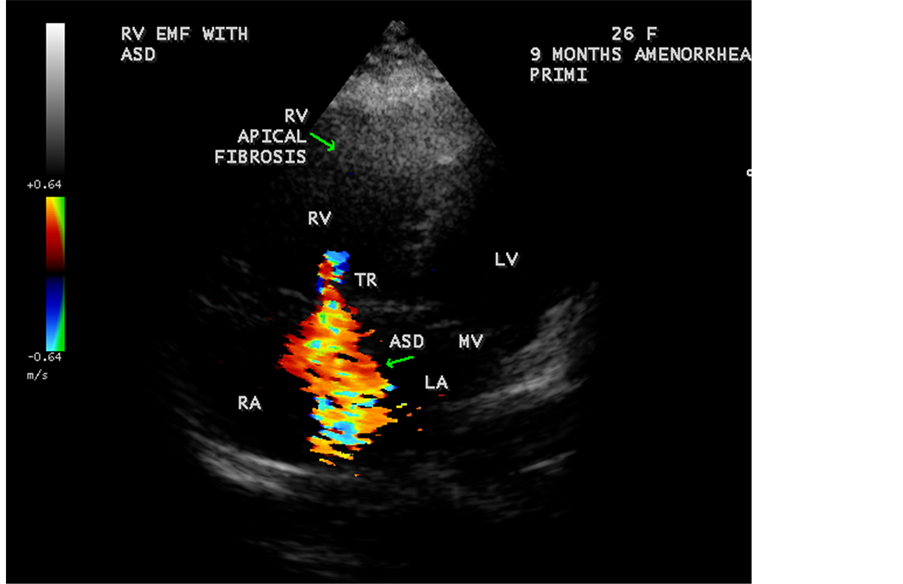

Figure 49. RV EMF with ASD in a 26-year-old female antenatally (Primi with 9 months amenorrhea).

A left ventricular EMF mimicking apical left ventricular hypertrophic cardiomyopathy as shown in Figure 23, Figure 24 and Figure 25 in a 2-year-old male child and an apical right ventricular hypertrophic cardiomyopathy in a 60-year-old female as shown in Figure 26 mimicking as right ventricular EMF had been found by Transthoracic echocardiographic screening. A right ventricular EMF associated with Psoriasis was shown in Figure 3 to Figure 7 in a 52-year-old male and a left ventricular EMF associated with pemphigus skin lesion in a 63-year-old male as in Figure 40 were detected in this region of Thoothukudi. RV EMF associated with congenital heart diseases such as ostium secundum atrial septal defect in a 26-year-old female antenatally (Primi with 9 months amenorrhea) as shown in Figure 49 and Figure 64 to Figure 66 in a 9-year- old girl. RV EMF associated with RV outflow tract disease (“Double chambered right

ventricle”) in a 16-year-old female as shown in Figure 50 to Figure 53 were detected. RV EMF with rheumatic involvement of mitral valve as shown in Figure 54 and Figure 55 in a 44-year-old female and in Figure 63 in a 55-year old female. Biatrial enlargement due to rheumatic atrioventricular (AV) valves (mitral and tricuspid) involvement characterized by stenosis of the valves are illustrated in Figure 56 to Figure 59 in a 54-year-old female and it is differentiated from EMF which is characterized by AV valve regurgitation as shown in Figure 34 and Figure 60. RV EMF associated with thickening and fibrosis of moderator band in a 16-year-old female was shown in Figure 46. RV EMF associated with apical left ventricular hypertrophic cardiomyopathy was shown in a 47-year-old male as in Figure 61 and in a 65-year-old female as in Figure 62.